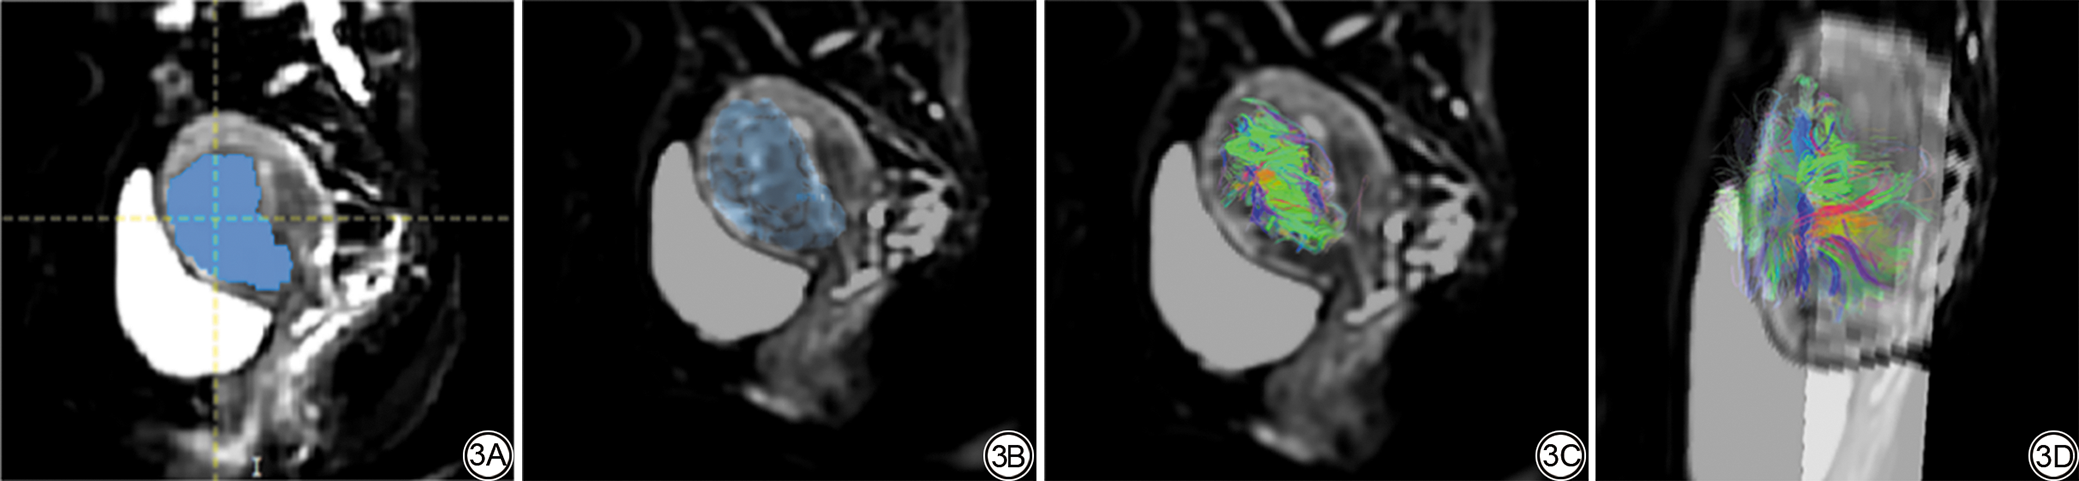

图3  女,42岁,腺肌病病灶感兴趣区(ROI)的勾画与纤维重建成果。3A:在TrackVis上逐层勾画病灶ROI;3B:以一个腺肌病病灶整体作为一个ROI;3C、3D:子宫腺肌病病灶区域纤维示踪重建结果,见大量环状走形纤维,长度中等,排列密集,混乱。

Fig. 3  Female, 42-year-old, results of delineation of adenomyosis lesion regions of interest (ROI) and fiber reconstruction. 3A: The lesion ROI is manually outlined slice by slice using TrackVis; 3B: The entire adenomyotic lesion is treated as a single ROI for fiber reconstruction; 3C, 3D: Fiber tractography of the lesion area revealed numerous circular and curved fibers with moderate length, densely distributed and disorganized in orientation.